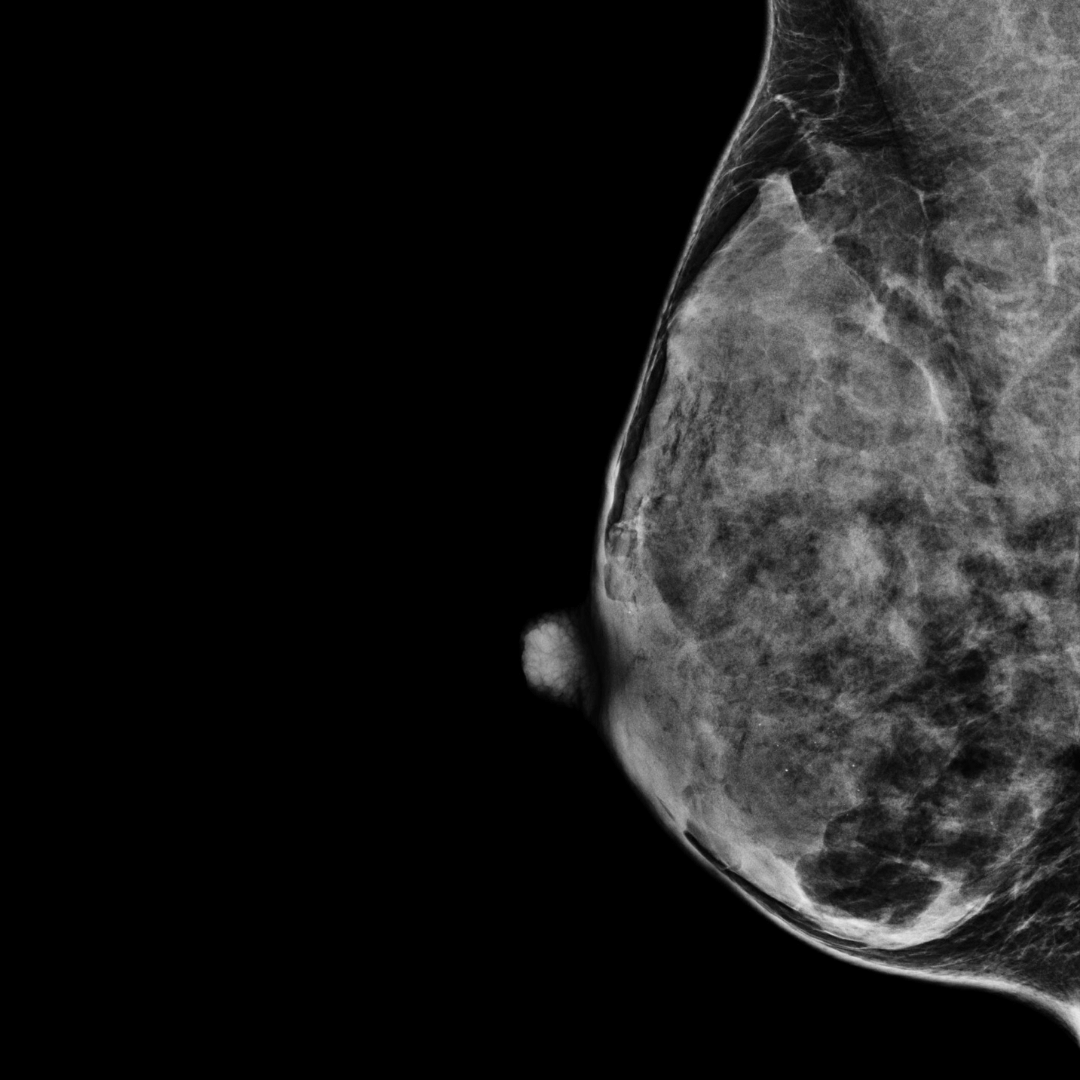

Category D

(most dense)

BI-RADS category D:

The breast tissue is almost all fibroglandular tissue and is extremely dense.